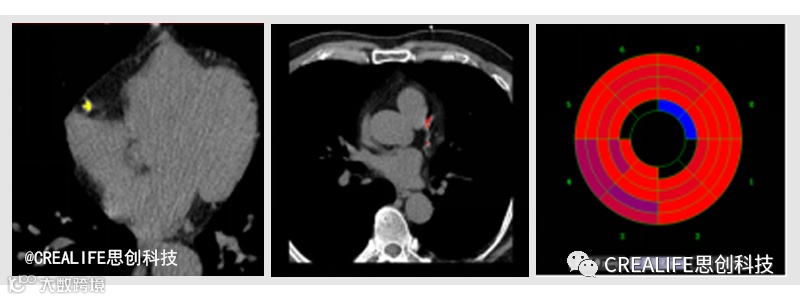

近年来,冠脉周围脂肪成像FAI技术引起心血管领域广大学者的关注,并成为研究热点。它是利用冠状动脉发炎后释放到血管周围脂肪组织的信号来抑制局部脂肪的形成,从而改变发炎的动脉血管周围脂肪成分,最终改变脂质对冠状动脉CTA衰减值的原理来实现。

为了更好地为临床医生赋能,实现临床和科研的进一步优化升级,思创科技再一次挑战智能冠脉周围脂肪分析(FAI)技术。此功能通过一键式智能操作,全方位展示血管周围脂肪分布情况,并且可对冠脉周围脂肪进行定量测量,自动分析计算得出脂肪分布衰减曲线、血管周围脂肪体积、曲线下面积等多项精准参数,从而指导临床早期识别并预防冠脉风险性疾病以及个性化药物治疗,最终实现提高心血管疾病患者救治率的目标。